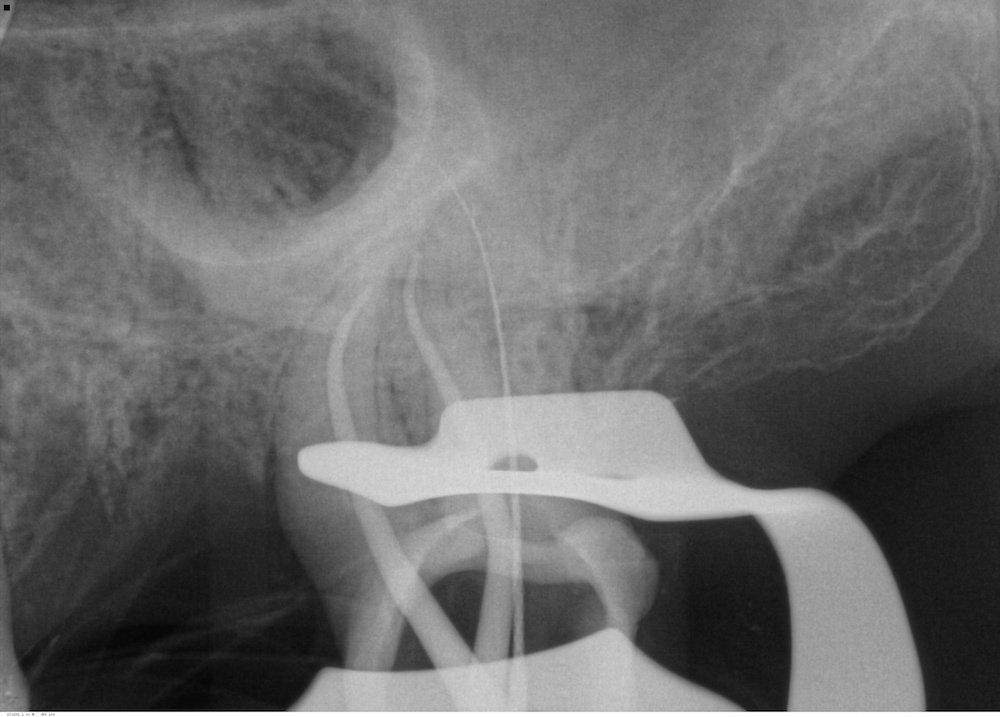

La tête de fragment est découverte à l’aide de limes U (taille 15/20) dégageant un diamètre de 0.5mm seulement. On glisse ensuite une boucle ajustable de fil autour du fragment.

Une fois serrée autour du fragment, celui-ci est extrait en tirant sur le fil.